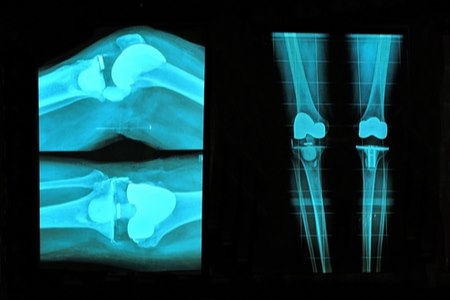

עד לפני שני עשורים בלבד, אדם שעבר ניתוח להחלפת מפרק הירך או ניתוח להחלפת מפרק הברך - נאלץ לבלות ימים ארוכים בבית החולים; ולאחר מכן, לעבור תקופת שיקום ממושכת, שנמשכה חודשים רבים.

לעומת זאת, כיום - מנותחים שעברו השתלת מפרקים מבלים (לרוב) יום-יומיים בבית החולים ומשוחררים לביתם, לתקופת שיקום הנמשכת כחודשיים עד שלושה חודשים בלבד, בממוצע.

ישנם מספר גורמים, שתרמו לקיצור תקופת השיקום, לאחר ניתוחי החלפת מפרקים. הדברים אמורים בפרט בניתוחי ברכיים (הכרוכים בתקופת החלמה קשה יותר ומצריכים שיקום אינטנסיבי יותר, בהשוואה לניתוחים להחלפת מפרק הירך).

בהחלט כן. מפרק הירך הוא מפרק פשוט יותר באופן משמעותי, בהשוואה למפרק הברך. כאשר אנחנו מנתחים את מפרק הברך, אנחנו משנים את המכניקה של המפרק. כפועל יוצא מכך, מטופלים לאחר ניתוח להחלפת מפרק הברך - צריכים לעבור טיפולי פיזיותרפיה יחסית אינטנסיביים.

התנועה של המפרק לאחר הניתוח שונה; והשרירים שיש להפעיל לאחר ניתוח להחלפת מפרק הברך, שונים אף הם. לכן, מטופלים לאחר החלפת מפרק הברך צריכים ללמוד מחדש איזה שרירים עליהם להפעיל; והם צריכים לעבור טיפולי פיזיותרפיה אמבולטוריים, באופן יומיומי לאחר הניתוח.